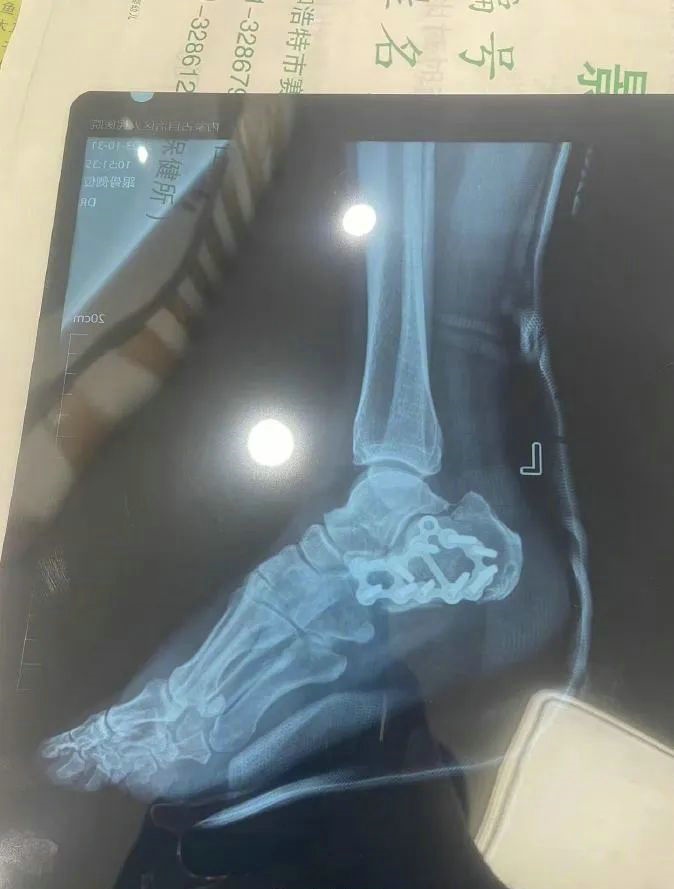

“那時(shí)候我剛工作了兩天,在第三天10月22日下午施工過程中從三層高的鐵架上摔了下來,導(dǎo)致30厘米左右的鋼筋刺穿我的右側(cè)臀部,左腳跟也粉碎性骨折,被送往內(nèi)蒙古自治區(qū)人民醫(yī)院救治,當(dāng)晚做了手術(shù)取出刺在右臀部的鋼筋,10月30日又進(jìn)行了左腳粉碎性骨折手術(shù)。”雷先生告訴記者。